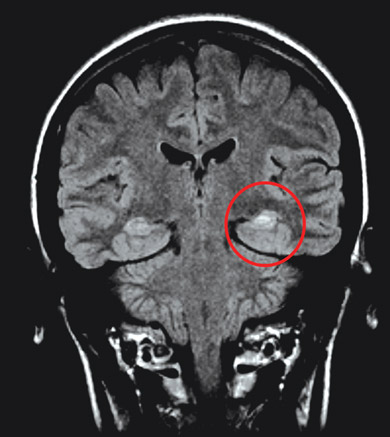

Neuroimaging: Nearly all adult patients with newly diagnosed focal seizures should undergo neuroimaging to assess for structural lesions of the brain, such as cerebral tumours, arteriovenous malformations, or scarring of the temporal lobe (hippocampal sclerosis). Magnetic resonance imaging (MRI) is the modality of choice, as it is superior to computed tomography in demonstrating subtle tissue changes such as those associated with an old ischaemic insult.4 However, it is essential that any structural findings are interpreted with caution and correlated with the clinical seizure characteristics and EEG findings, as structural lesions may be incidental (eg, diffuse white matter disease, lacunar infarcts, calcification, vascular spaces). Functional imaging modalities (such as positron emission tomography and single-photon emission computed tomography) can be used to evaluate patients who have medically refractory epilepsy and are being considered for surgical treatment, as these may provide additional localising information. Imaging may not be appropriate in children with typical benign focal syndromes, such as benign rolandic epilepsy and occipital epilepsy.

Janice was referred to a neurologist, who ordered an EEG and high-resolution MRI of her brain. The interictal EEG showed spikes of electrical activity in the left temporal lobe (Box 2) with predominance in the anterior temporal region. The MRI revealed atrophy of the left hippocampus with an associated increase in signal intensity (Box 3).

Hippocampal sclerosis is the most commonly identified pathological lesion in mesial temporal lobe epilepsy. A history of febrile seizures in infancy may be a marker of the condition in a minority of patients, such as Janice. Whether hippocampal sclerosis is a cause or an effect of seizures is uncertain.2